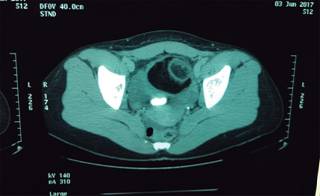

Mujer de 30 años de edad, valorada dos días antes por otro servicio médico y egresada con diagnóstico de síndrome de intestino irritable y tratamiento a base de antiespasmódicos (butilhioscina), sin mejoría del cuadro clínico. Como antecedentes de importancia refiere trastorno funcional digestivo de aproximadamente cinco años de evolución, para el que ha recibido múltiples tratamientos farmacológicos, entre ellos trimebutina y bromuro de pinaverio/dimeticona con mejoría parcial de la sintomatología. Las últimas dos semanas ha estado en tratamiento con complejo B + diclofenaco por un desgarro muscular inguinal derecho, según refiere. FUM 14/05/2017, ritmo regular 30 × 5, dismenorrea leve, G0, MPF: preservativo. En esta ocasión acude a nuestro servicio de urgencias refiriendo dolor abdominal de inicio insidioso un par de horas antes de su ingreso, localizado a nivel del flanco y fosa iliaca derechos, intenso 8/10, tipo cólico, sin claros atenuantes ni exacerbantes que la obliguen a adoptar posición antálgica, el cual se irradia hacia la FID y hacia el hipogastrio y se acompaña de escalofríos, náusea y vómito en tres ocasiones de contenido biliar, hiporexia, además de estreñimiento, evacuaciones en escíbalos (tipo 5 de la escala de Bristol) sin moco ni sangre que no mejoran las molestias abdominales y flujo vaginal escaso transparente, no fétido. Al interrogatorio dirigido negó fiebre o sensación de alza térmica y sintomatología urinaria. A la EF destaca paciente que adopta posición antálgica, con intenso dolor abdominal que incluso le provoca llanto, hemodinámicamente estable, con signos vitales dentro de parámetros normales, sin taquicardia, sin hipertensión y sin fiebre. Pálida, bien hidratada. Abdomen globoso, distendido, blando, depresible, con resistencia muscular y dolor a la palpación media y profunda en flanco y fosa iliaca derechas, con apendiculares positivos y datos francos de irritación peritoneal. Se palpa tumoración renitente a nivel del hipogastrio, de bordes regulares desplazable y no adherida a planos profundos, timpanismo a la percusión de marco cólico, mate en el hipogastrio. Laboratorios: sin anemia, leucocitos normales (8.5 10*3/UL) con neutrofilia de 75 %, sin bandas, PFH’s, electrolitos séricos y enzimas pancreáticas normales. EGO patológico: en el examen microscópico con 15-20 leucos por campo, 8-10 eritrocitos por campo, células escamosas escasas y bacterias moderadas, nitritos negativos. Radiografías simples de abdomen (Figuras 1 y 2): imagen irregular con densidad de calcio proyectada en el hueco pélvico. TAC de abdomen simple y con contraste IV (Figura 3): hacia hueco pélvico, superior a la vejiga y que condiciona desplazamiento ascendente de asas intestinales y compresión extrínseca y desplazamiento del recto. Se observa lesión ovoidea definida de 8 × 7.8 × 10.4 cm, de densidad heterogénea a expensas de contenido hipodenso, -112 UH que corresponde con grasa y calcificación gruesa a la periferia del borde inferior. Probablemente dependiente del anexo derecho. Resto de estudio sin alteraciones, incluido el apéndice. Resultó difícil controlar el dolor abdominal de la paciente, pues requirió trimebutina, paracetamol, ketorolaco, clonixinato de lisina/pargeverina y tramadol, por lo que se sospechó compromiso vascular de la lesión quística pélvica por torcedura de su pedículo principal. Con lo anteriormente mencionado se diagnosticó abdomen agudo secundario a teratoma ovárico probablemente torcido, por tal motivo fue sometida a LAPE de urgencia (Figura 4). Histopatología. Teratoma quístico maduro de 14 cm de eje mayor con datos de isquemia y hemorragia reciente y extensa. No hay presencia de células neoplásicas.

Figura 3: TAC simple de abdomen: lesión ovoidea definida de 8 × 7.8 × 10.4 cm, de densidad heterogénea a expensas de contenido hipodenso, que corresponde con grasa y calcificación gruesa a la periferia del borde inferior. Probablemente dependiente del anexo derecho.